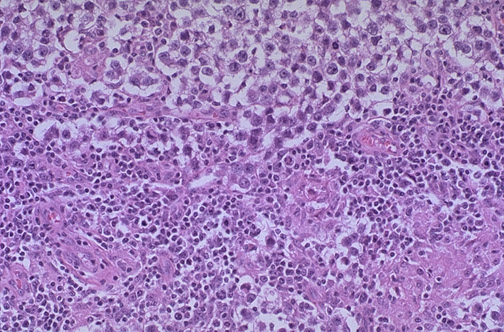

This is the histologic pattern of the typical seminoma. Lobules of neoplastic cells have an intervening stroma with characteristic lymphoid infiltrates. The seminoma cells are large with vesicular nuclei, and pale watery cytoplasm.